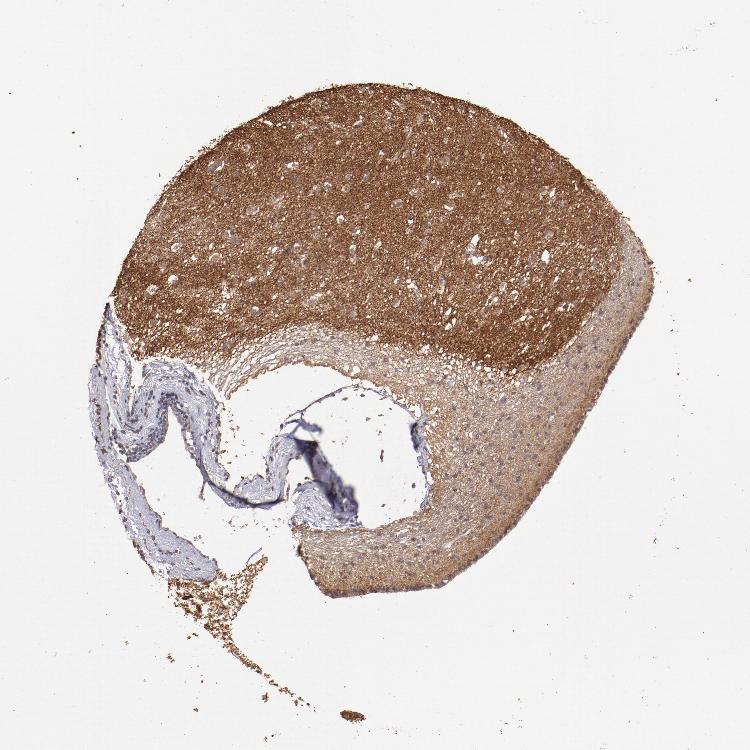

CAUDATE - Antibody stainingi

Antibody staining in the annotated cell types in the current human tissue is reported as not detected, low, medium, or high, based on conventional immunohistochemistry profiling in selected tissues. This score is based on the combination of the staining intensity and fraction of stained cells.

Each image is clickable and will lead to virtual microscopy that enables deeper exploration of all samples and also displays staining intensity scores, fraction scores and subcellular localization as well as patient and tissue information for each sample.

Antibody HPA001869Antibody HPA023882

Glial cells HighNot detected

Neuronal cells HighLow